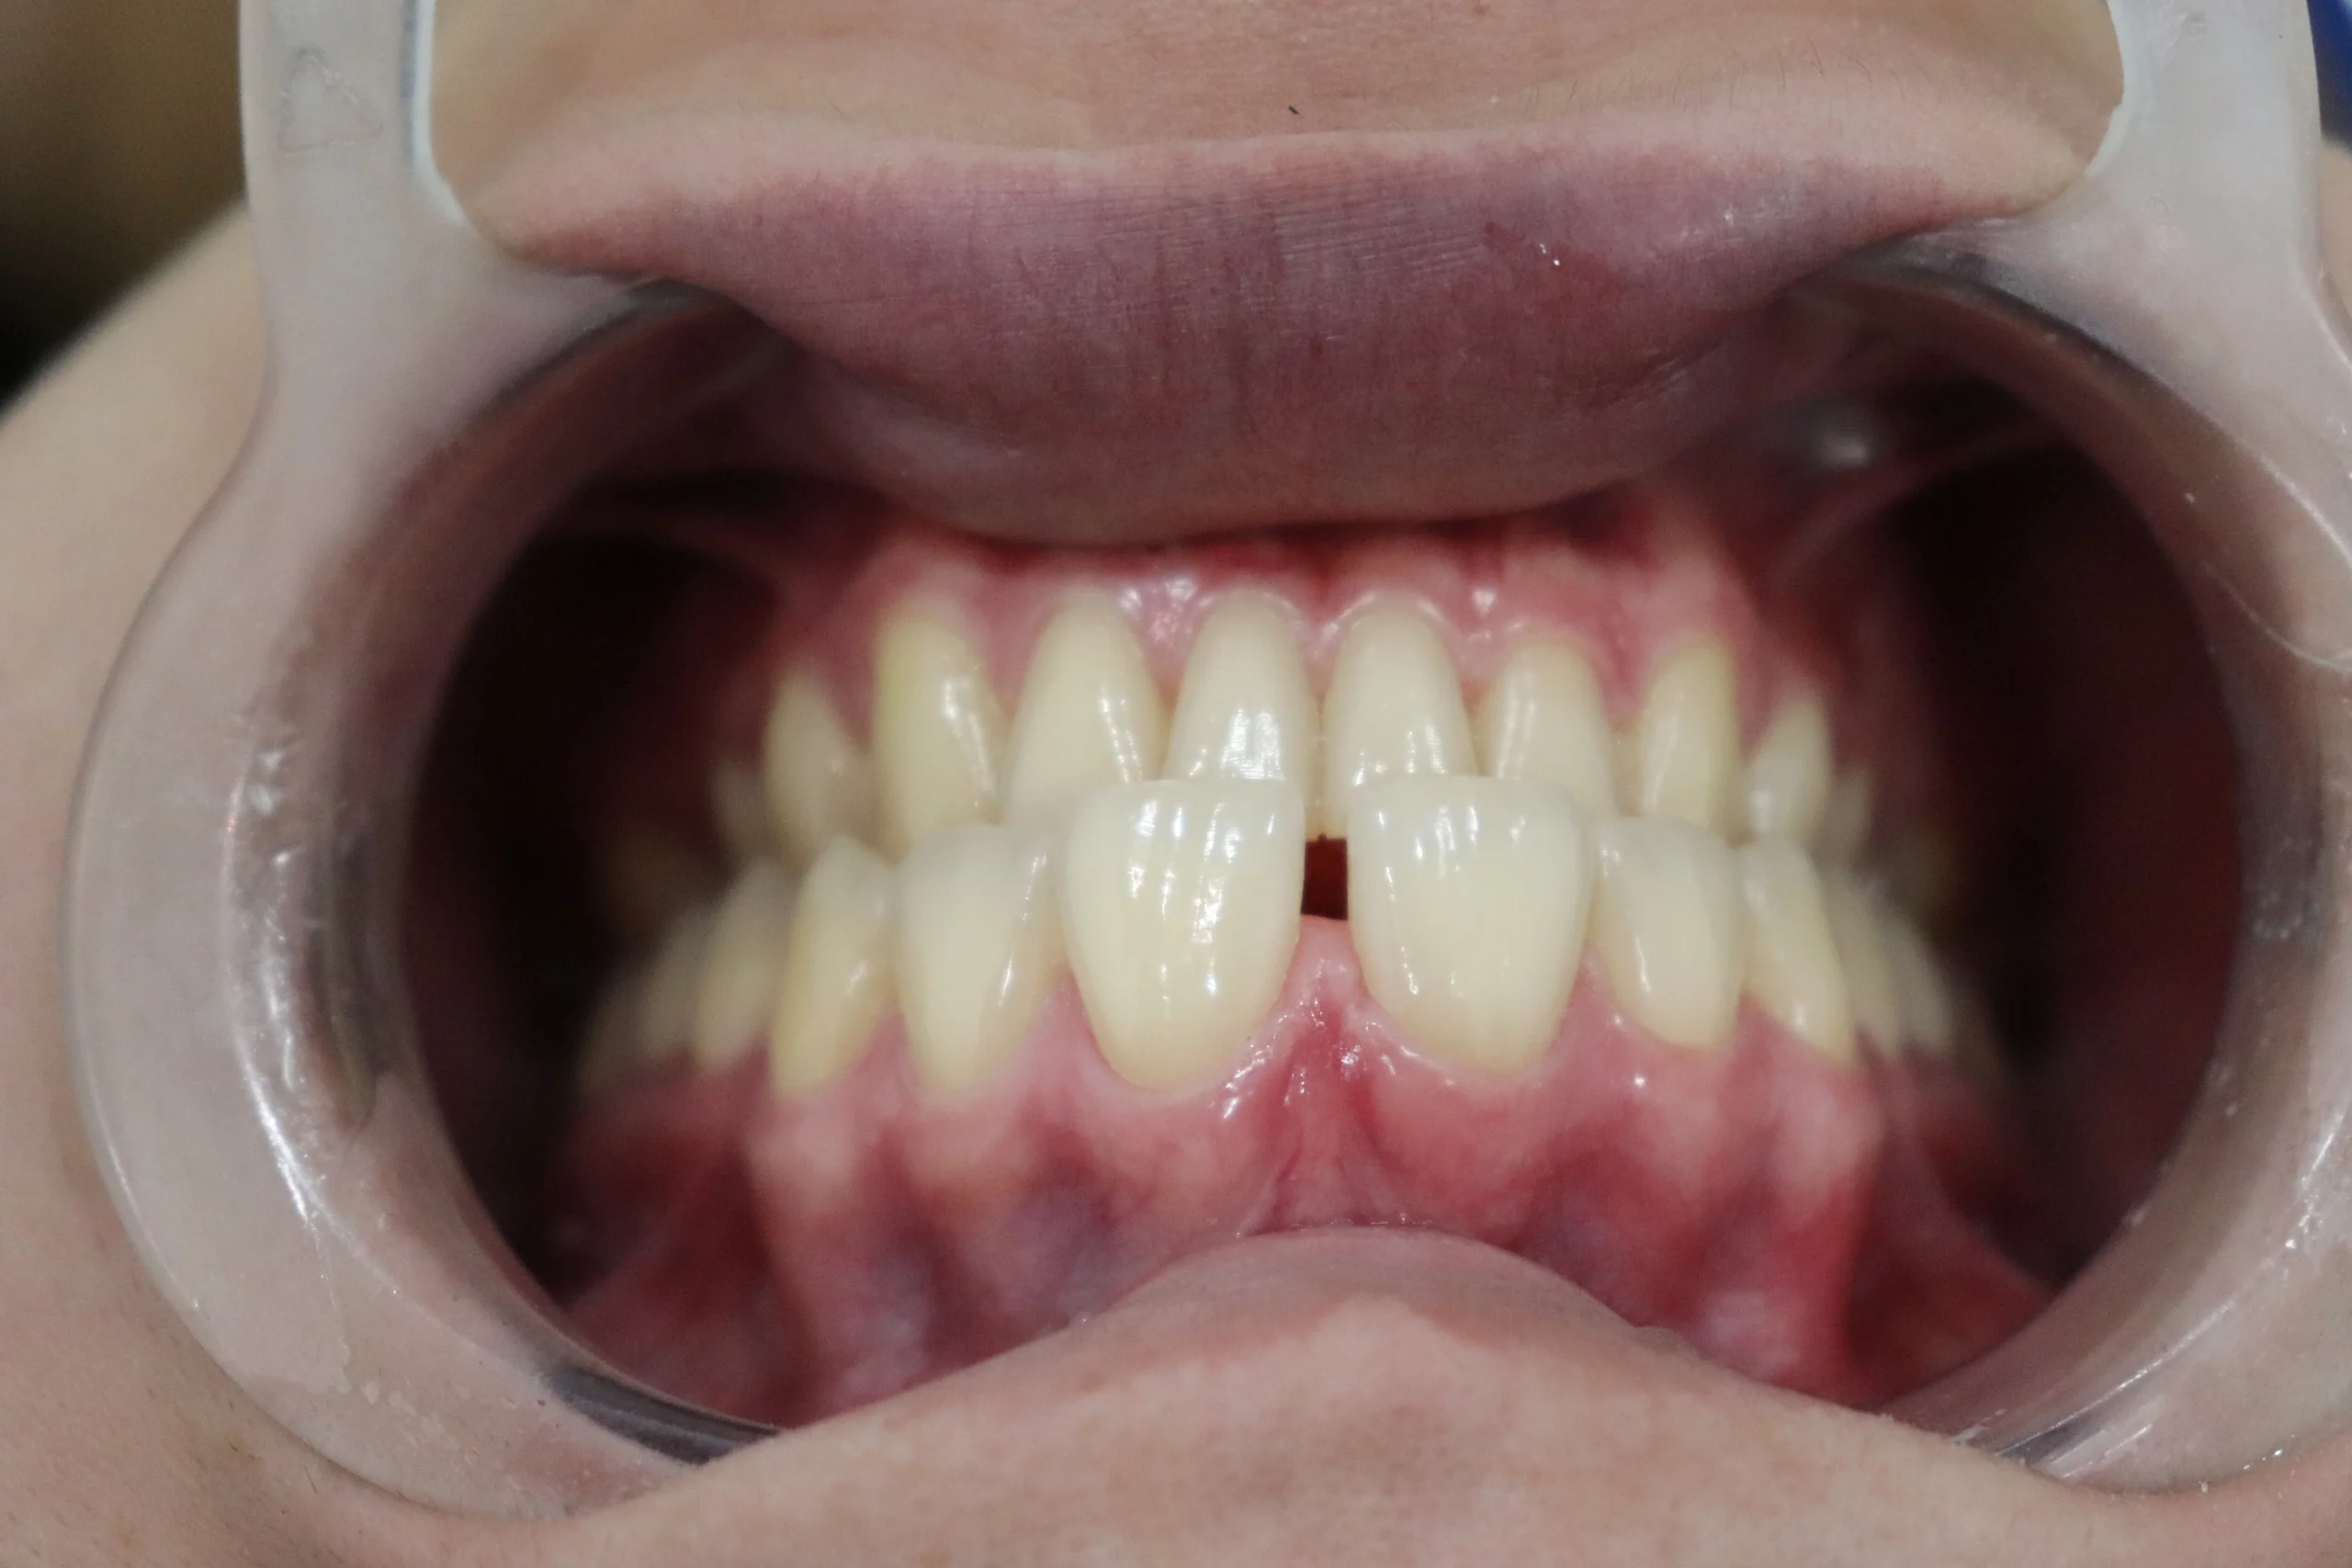

Finalmente, se decidió realizar un cierre de diastema utilizando resina compuesta, una técnica conservadora y altamente estética que permite corregir el espacio sin desgastar el esmalte dental.

Después